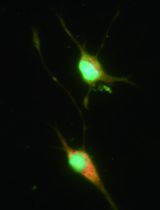

Bone marrow-MSCs (BM-MSCs) were isolated from femurs of Lewis and Fisher rats (200 g). In brief, the bone shaft was extracted inserting a 22 G needle and flushed out with alpha-MEM supplemented with 10% FBS and 2 mM EDTA and cell clumps desegregated. The cell suspension was centrifuged at 400 x g for 20 min at room temperature. Rat BM-MSCs were seeded and expanded in alpha-MEM supplemented with 10% FBS (Ramírez-Bajo et al., 2020a). Therefore, BM-MSCs were characterized according to standardized criteria defined by International Society for Cellular Therapy (ISCT) (see Note 1; Figure 1).

Figure 1. Representative images of MSCs characterization by flow cytometry and multi-lineage differentiation potential. A. Flow cytometry analysis of MSC. Cells were positive for surface stem cell markers (CD44, CD29 and CD90), and negatives for endothelial (CD31), and hematopoietic (CD45) markers. B. Adipogenic differentiation (x200 magnification) as demonstrated showing positivity for oil red staining. C. Osteogenic differentiation (x100 magnification) as demonstrated showing positivity for alkaline phosphatase activity, and was revealed by SigmaFast BCIP/NBT chromogen staining.

According to standardized criteria defined by ISCT’s guidelines, MSCs must a) be plastic adherent when kept under standard culture conditions, b) positively expressed MSC markers (CD29, CD44, and CD90) and negatively endothelial (CD31) and hematopoietic lineage (CD45) markers, and c) retain a multipotent phenotype with the ability to differentiate in adipogenic and osteogenic lineage under the standard differentiation conditions (Figures 1B-1C).